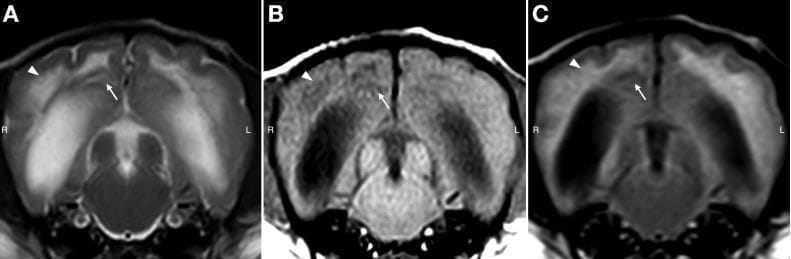

Transverse MRI images with T2-wighted (T2W) sequences (A), T1-weighted (T1W) sequences (B), and T2-FLAIR sequences (C). The inclusion criteria of brain MRI were dogs demonstrating intra-axial T1W iso- to hypointense,T2W and T2-FLAIR hyperintense lesions (arrowheads), with ≥ 1 lesion suggestive of a necrotic/cystlike lesion characterized by being hyperintense on T2W and hypointense on T1W and T2-FLAIR images (arrows).

R = Right. L = Left.